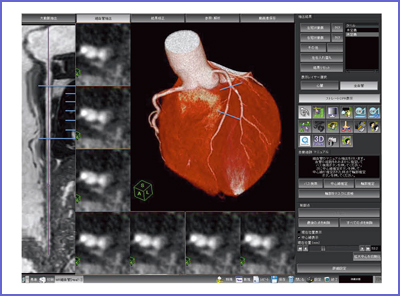

ラットの断面解剖アトラス。ラットの断面解剖アトラス - メルカリ。ラットの断面解剖アトラス。熊本県産ヒノヒカリ 30kg。 B 中古品としては綺麗と判断した商品。一般中古よりは状態の良い商品。 C 中古品として一般的な状態の商品。やや使用感があり、日焼けやキズなどがみられる場合がある商品。 D 中古品と考えても、気になる汚れやキズなどがある商品。。[A12303631]陽性・陰性症状評価尺度(PANSS)マニュアル。暫間ミニインプラント療法/永田睦(著者)。[A11078446]新生児学テキスト [単行本(ソフトカバー)] 一般社団法人 日本新生児成育医学会。改訂版・神経内科のスピード学習と専門医学習/泉義雄,五十棲一男【著】。[A12335451]徹底討論! ハートバルブ・カンファレンス。Ea-080/化学両方の領域 2016年4月号 Vol.32No.4 医薬ジャーナル社 2016年3月25日発行 特集:食の安全と微生物汚染 医療 医学 薬学/L1/61121。シノプティック・マテリア・メディカ 4訂/F.ヴァーミューラン(著者),RAH著(著者)。8K0098◆連続写真と動画で学ぶ 白内障手術パーフェクトマスター 基本から難症例への対処法まで 谷口重雄 ▽。[A01906937]すぐわかる小児の画像診断 改訂第2版 (画像診断別冊KEYBOOKシリーズ) [単行本] 荒木 力、 原 裕子; 野坂 俊介。IVR-手技,合併症とその対策 Interventional/石橋忠司(著者),山田章吾(著者)。眼光学 1 眼内レンズ/市川宏(著者)。[A11048022]造血器腫瘍アトラス 形態、免疫、染色体から分子細胞治療へ 谷脇 雅史、 横田 昇平; 黒田 純也。カラー図解 脳神経ペディア 「解剖」と「機能」が見える・つながる事典/渡辺雅彦(著者)。培養細胞実験ハンドブック 改訂 基本から最新の幹細胞培養法まで完全網羅!/黒木登志夫(著者),許南浩(著者)。[A01564935]病院の世紀の理論。機能性食品の作用と安全性百科/上野川修一(著者)。[A01351009]ICUブック 第4版。整形外科スタンダード手術基本手技/山本眞(著者)。H19-047 醫學博士 茂木藏之助 著 茂木外科總論 南山堂 書き込みあり。。胃 形態とその機能 第2版 形態とその機能/川井啓市(著者)。[A12326342]リウマチ・膠原病アトラス 廣畑 俊成。日経デジタルヘルス年鑑(2017)/日経デジタルヘルス。[A12090911]硬膜動静脈瘻塞栓術ハンドブック [単行本] 滝 和郎。[A11248770]一歩進んだ麻酔管理~常識は常に真実か?~ 国沢 卓之。[A12333909]睡眠とてんかん: その密接な関連性。[A12335621]バスキュラーアクセスのトラブルシューティング ─ 電子版付 ─。[A12344518]改訂第6版 救急診療指針 上巻 (上巻)。ネッター解剖学図譜 第2版/相磯貞和(著者)。[A01204523]EBMによる糖尿病経口薬の選択と適正使用。【まとめ/訳あり】緑内障 11冊セット 眼科/診療/薬物治療/ガイドブック/【2211-041】。[A12325943]不整脈 識る・診る・治す (循環器内科専門医バイブル) [単行本] 平尾見三; 小室一成。[A11760723]領域横断的がん取扱い規約。[A12325147]イラストでイメージする 小児の心エコー 第2版 (第2版)。眼科手術学/ゲオルク・アイスナー(著者),渡辺郁緒(著者)。[A12309814]診断と治療2019年増刊号。[A12357725]頭頸部がん手術ノート 輪層の外科。[A11067697]CTパターンから理解する呼吸器疾患: 所見×患者情報から導く鑑別と治療 門田 淳一。★カラーフォト皮膚病1★籏野 倫★。胸部CTの異常陰影/松原義人(著者)。[A12301703]オルソケラトロジ-・ハンドブック トッド・D.ウィンクラ-、 ロジャ-・T.ケイム; 日本オルソケラトロジ-協会。[A12343460]小児画像診断の勘ドコロNEO。DVD SPAT 頚椎・胸椎編/鹿島田忠史(著者)。[A11550186]腸疾患診療―プロセスとノウハウ。和蘭薬鏡(全) 科学書院。脳神経外科臨床マニュアル 改訂第5版/端和夫(編者),三國信啓(編者)。[A11185929]脊椎・骨盤の外傷手技のコツ&トラブルシューティング [DVD付] (OS NOW Instruction)